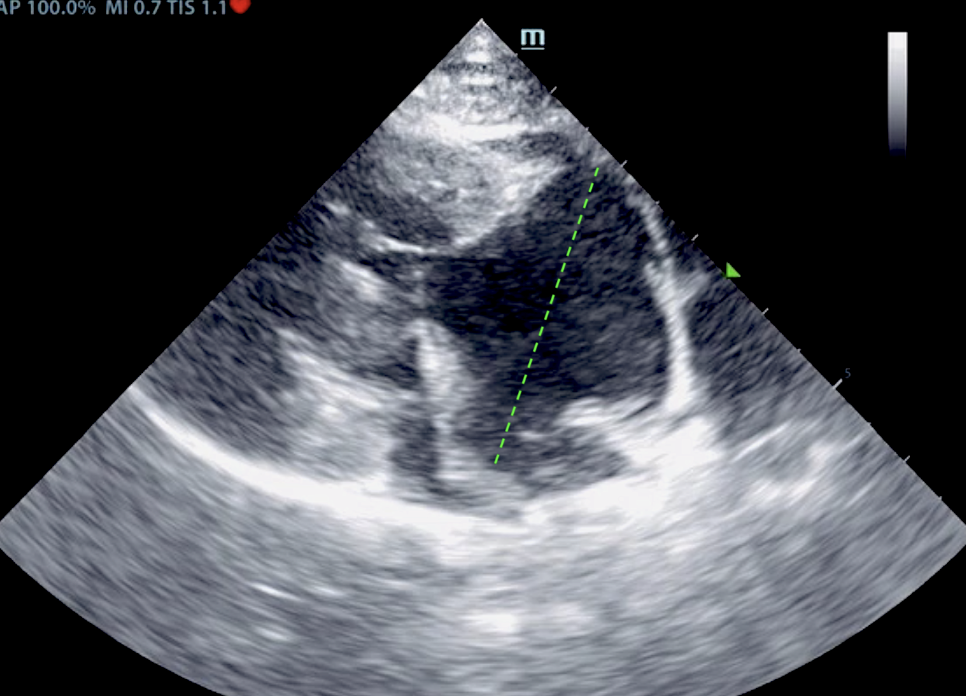

Our experienced SDEP® certified technicians, Kelly Reschny, RVT & Crystal Hill, RVT will come to your clinic and perform a diagnostic ultrasound on your patient. The images will then be submitted to a SonoPath specialist who will provide a comprehensive report. The report will include sonographic findings, internal medicine diagnostics and treatment recommendations with annotated images identifying any pathology or areas of concern. If needed, our technicians can perform ultrasound-guided fine needle aspirates, abdominocentesis or pericardiocentesis.

The Focal Zone fueled by Sonopath, a mobile veterinary ultrasound service, gives you a sneak peek on its monthly Star Cases.

VSD, CHF, and Thoracic Mass In A 4-Year-Old Intact Male Sphynx Cat: Our 2023 Star…